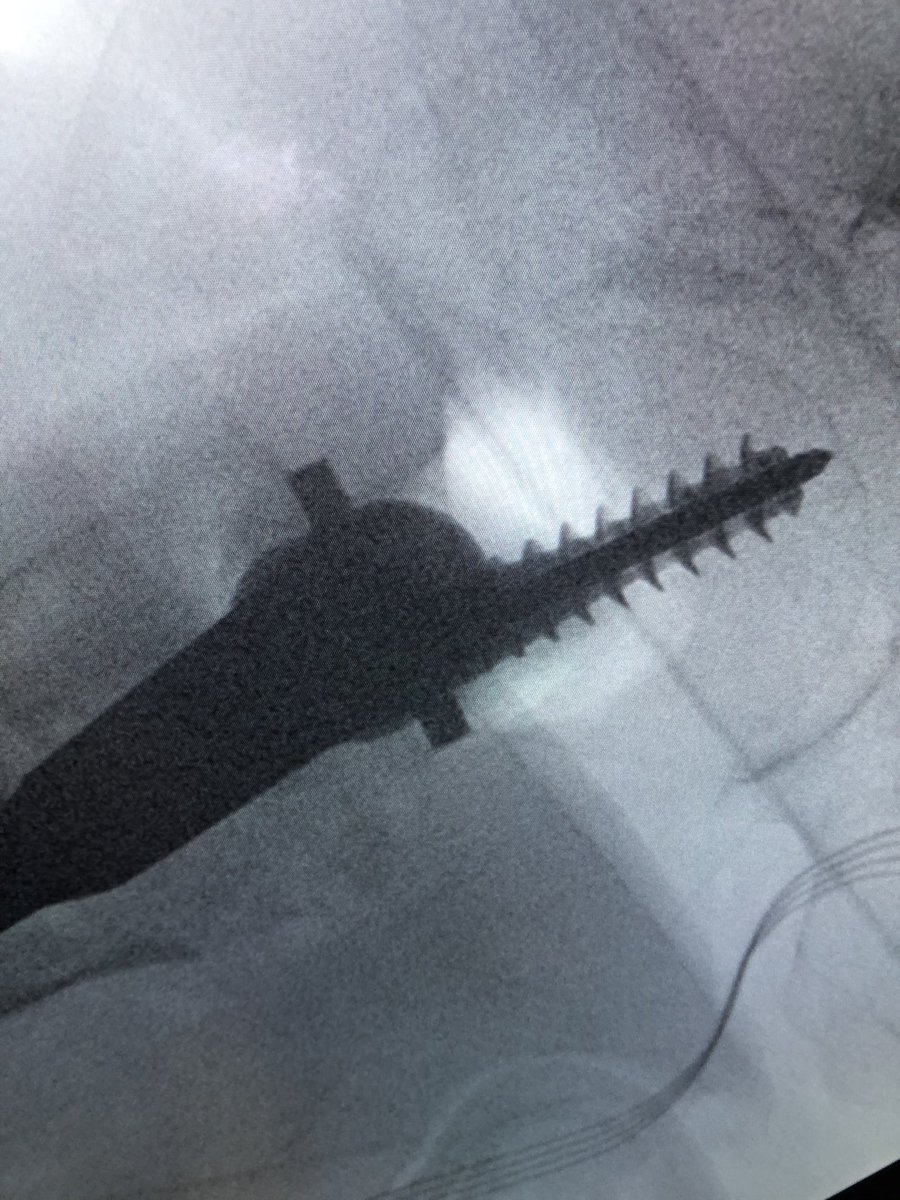

[1/2] Always make sure your wire stays where you put it. The original wire placement for drilling was this, but after drill came out so did the wire, and the screw was placed over the wire without ascertaining that it was back in proper position...

[2/2] This resulted in a completely different (anterior) trajectory of screw placement (left), which then had to be corrected (right). So always check.